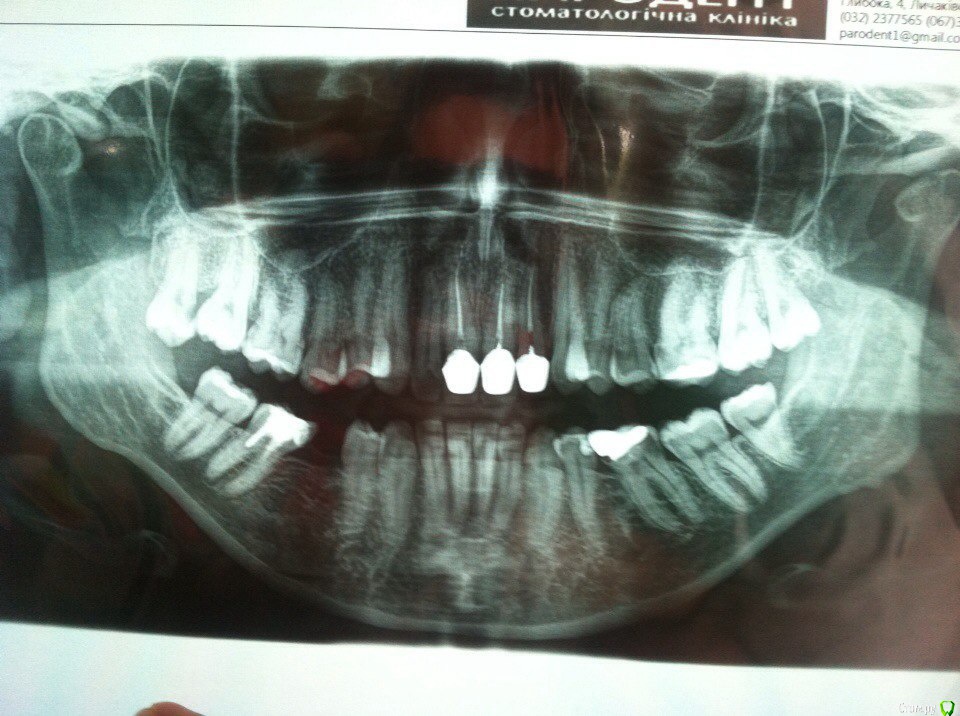

Oksanater Опубликовано 22 июня, 2016 Поделиться Опубликовано 22 июня, 2016 Здравствуйте.У меня глубокий дистальный прикус. Ноет правый суглоб. После некоторого изучения проблемы, я решила все таки обратится в клинику, где в стоматологии работает остеопат. Выбрана тактика остеопатического выдвижения нижней челюсти вперед совместно с ношением капы ночью. Предварительно ориентируются на 2 месяца такого лечения (мне 34 года). После этого в плане брекеты на верхнюю и нижнюю челюсть, которые переместят зубы в правльное положение, и возможно протезирование боковых зубов, где будет сильная диокклюзия.Что меня смущает. И что прошу проккоментировать:на первом приеме был сделан только слепок для капы, но остеопат "вставил челюсть" и отпустили домой, до следующего приема через две недели, когда дадут капу. Челюсть действительно подалась вперед, даже на следуещее утро пришлось ехать к стоматологу чтоб спилить коронки на верхних резцах, т.к. они поставлены взамен крывых своих зубов и сделаны намного толще (видимо чтоб создать типа смыкание с нижнимы зубами). Нижние резцы стали ударятся о верхние, но после обпиливания стало лучше. По прошествию суток чувствую, что челюсть все равно потихоньку занимает прежнее положение.У меня возникло опасение по поводу такого лечения. Не будет ли только ночное ношение капы просто расшатывать суглобы, не приведя к стойкому выдвижению?Если в моем вопросе помимо снимков все же нужны фото, то сделаю. Пока не делаю, т.к. после "вправления" как-то странно закрываю у "укладываю" зубы и очень напряжены мышцы нижней трети лица. Ссылка на комментарий

m.d.n Опубликовано 22 июня, 2016 Поделиться Опубликовано 22 июня, 2016 реконструкция оклюзионной плоскости нужна.выкладывайте фото .Так же кт суставов нужно , и гипсовка в артикулятор Ссылка на комментарий